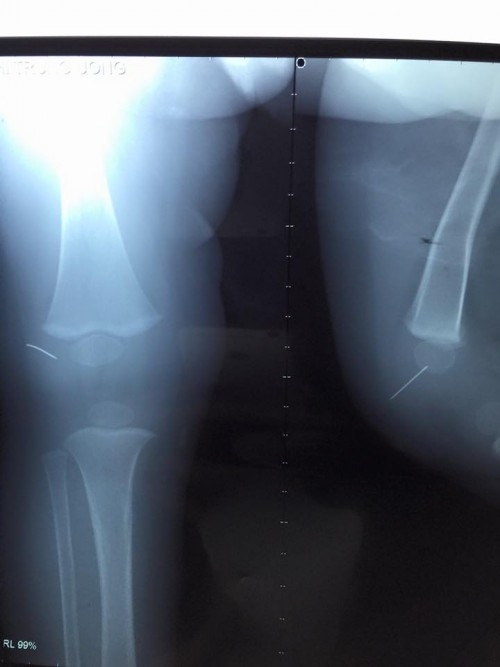

Hình ảnh chụp phim xác định dị vật kim khâu trong khớp gối của bệnh nhi |

Các bác sĩ Bệnh viện Nhi TƯ vừa phẫu thuật lấy ra khỏi khớp gối của bệnh nhi 1 tuổi một đoạn kim khâu diều dài chừng 1,5cm.

Sau khi chụp phim, làm các xét nghiệm, bệnh nhi được chỉ định phẫu thuật. Theo BS Lê Tuấn Anh, khoa Chỉnh hình nhi, điều đáng nói là dị vật này rất mảnh và không cố định nên các bác sĩ đã rất khó khăn trong việc xác định vị trí và thực hiện phẫu thuật. Chính vì vậy khi mở bao khớp gối của bệnh nhi, bác sĩ đã không tìm thấy dị vật. Sau đó nhờ sử dụng máy X-quang tăng sáng, hỗ trợ định vị dị vật, các bác sĩ phát hiện đoạn kim đã găm vào xương bánh chè của trẻ. May mắn cuộc phẫu thuật đã thành công.